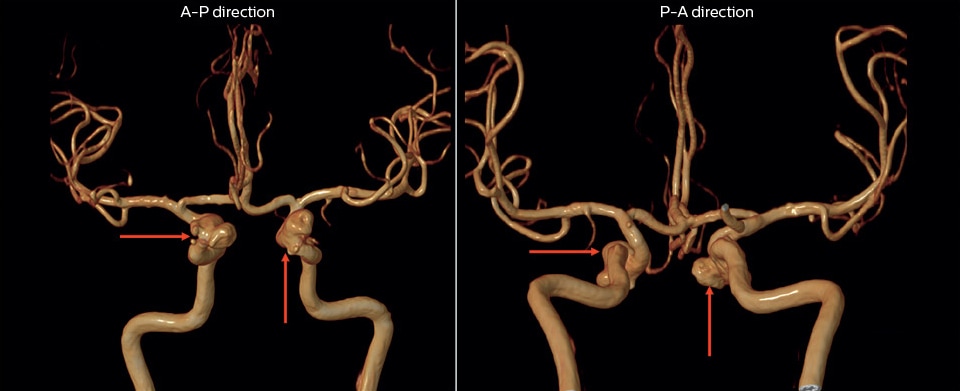

“The 3D TOF MR angiograms are obtained by using 3D T1- weighted FFE sequences (TR 35 ms, TE 7 ms, flip angle 20 degrees, field of view 250 × 190 × 108 mm, matrix 732 × 1024, four slabs, 180 slices of 0.8 mm thickness, acquisition time 8:56 minutes). On our Achieva 3.0T MRI system with an 8-channel head coil, 3D TOF is easy to use and the background signal suppression is very good. Maximum intensity projections (MIPs) and volume-rendered images are reconstructed from the data. We use a single-artery highlighting method to reduce arterial overlay. The method can also be used for carotids or other small intracranial vessels.”

“Advances in MR imaging, the high SNR and spatial resolution of 3.0T, increasing observer experience and improved postprocessing techniques have improved the capabilities of MRA over the last decade. We found that 3D TOF MRA provides excellent images for the visualization of small cerebral aneurysms which enables us to accurately diagnose, and this accuracy appears to be similar to that obtained with DSA according to data from a 2014 study," [2] Dr. Li says.   “Aneurysm location can influence how easy it is recognized. Infundibula can mimic aneurysms, adding to the difficulty of interpretation. On MIP images, small aneurysms can also be easily misinterpreted when the aneurysm overlaps with the vessel. This is why in our method we are viewing the images from multiple angles.”   “In the hundreds of patients with aneurysms that we scanned, we saw no significant differences in accuracy, sensitivity or specificity among the locations. [2] We think this is the result of technical advances in image acquisition and postprocessing algorithms.”